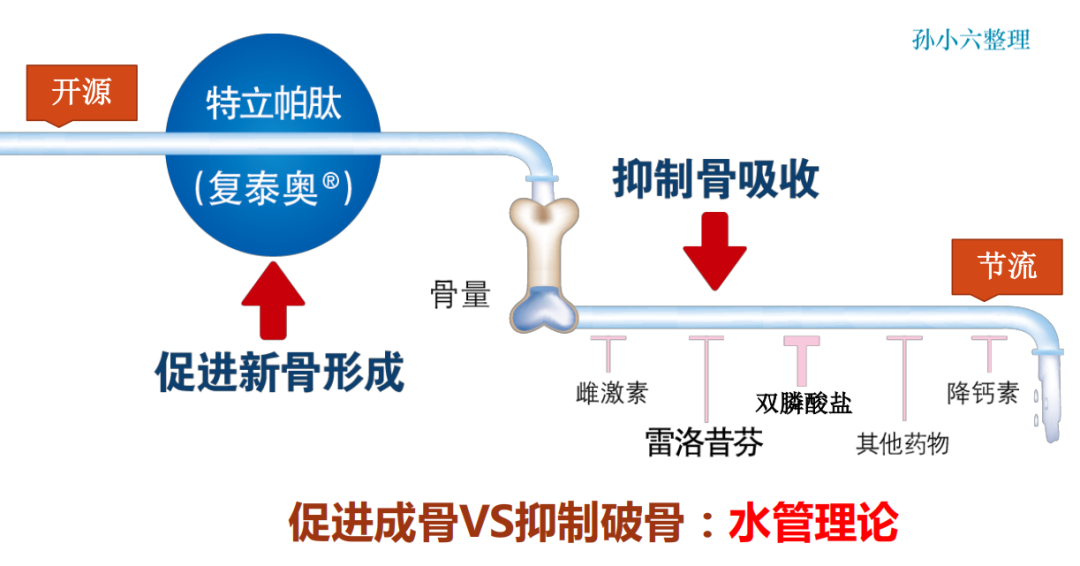

2、骨形成促进药

甲状旁腺激素类似物,以特立帕肽为代表,具有强大的促骨形成的作用,一般认为,其抗骨质疏松作用强于抗骨吸收药物。

适用于绝经后、男性和糖皮质激素性骨质疏松症以及高骨折风险患者的治疗。

1、骨吸收抑制药

①双膦酸盐类:

双膦酸盐类是目前临床上应用最为广泛的抗骨质疏松症药物。

能抑制骨吸收,减少骨丢失,并有止痛作用。

其作用机制是通过抑制体内破骨细胞活性,使骨转化率下降,从而减少骨质的丢失。

②降钙素(CT)类:

降钙素能抑制破骨细胞的生物活性和减少破骨细胞的数量,可预防骨量丢失并增加骨量。

④雌激素类药物:

此类药物只能用于女性患者。雌激素类药物能抑制骨转换,阻止骨丢失。